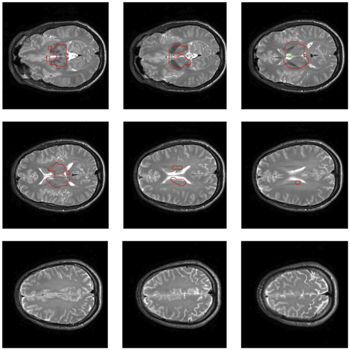

We located the bursts in brain tissue of all slices except around the periventricular area (probably due to movement induced by ventricular pulsation in those regions [31]) as illustrated in figure A2.

Further, we explored the signal distribution over the entire brain. 9 slices (in 5 volunteers) were acquired at different positions, with slices from the bottom to the top covering all anatomical regions.

Standard image High-resolution imageFigure A2. 9 Anatomical slices which correspond to the positioning of the EPI time series. Tissue surrounded by red drawing showed no ZQC bursts.

Download figure: